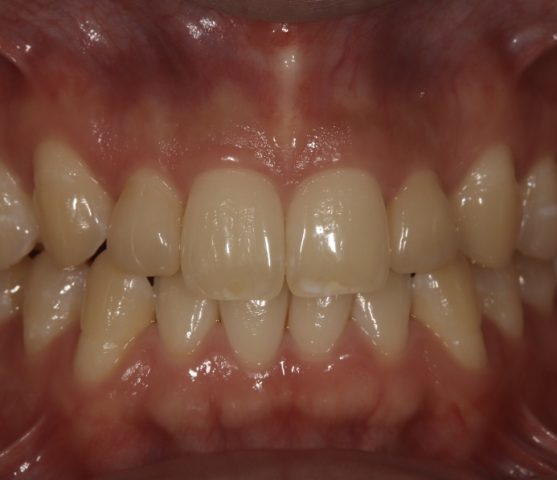

Before

After

| 診断名 | セラミックインレー審美補綴治療 |

| 年齢・性別 | 50代・女性 |

| 治療期間・回数 | 2週間~3週間/2回 |

| 治療方法 | セラミックインレーによる審美補綴治療 |

| 費用 | 55,000円(税込み) |

| デメリット・注意点 | 保険が適用できないため自費診療になる。 セラミックスインレー・クラウンに強い力がかかると割れてしまう恐れがあるため、歯ぎしりや食いしばりが癖になっている患者様にはおすすめできない場合がある。 |